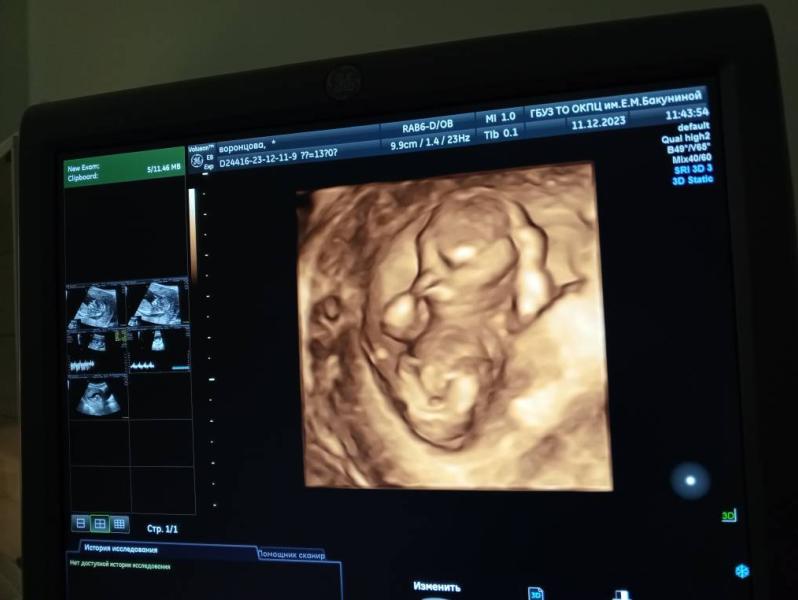

Девчонки, покажите первые фотки со скрининга. Нюмы сегодня прошли, малыш здоров🥰😍 развивается в срок. А фотка вообще ничего не понятно😅

Вот у нас сбоку там такие же, а основное фото типо 3д включили вообще не понятно ничего, я аж испугалась сначала 😅😅